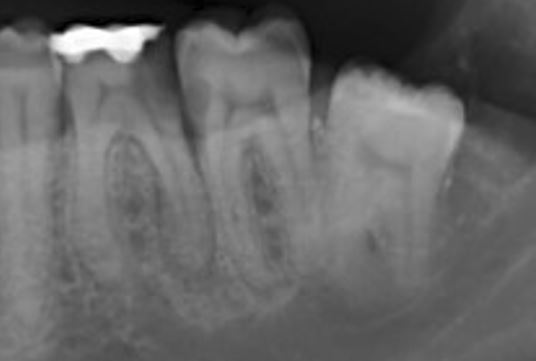

- Het duurt vaak wel tot een jaar tot de ontsteking niet meer zichtbaar is , Alleen als de zenuw nog leeft Links onder heeft een groot gat {Dit lijkt ook zo was ook een vlekje.

- Toen element 36 was weg gefreesd was er alleen een vlekje te zichtbaar op element 37 dat zo was weggepoetst

De weledelgeleerde tandarts Padrao zag op dezelfde foto maar dan de originele foto hieronder op element 36 een groot gat tot aan de furca ( kaakbot niveau ) en op element 37 een pericaal apicaal ontsteking .

Op de fotos van 12-11-2021 is er volgen tandarts Henk niets bijzonders te zien . Ik zie nu dat er op de fotos van 12-11-2021 geen wortelpunt ontsteking te zien is dat kan . Verder had de tandarts Henk kunnen zien dat er een tijdelijke vulling in zat De wortelkanaalbehandeling niet is afgemaakt

De fotos van 21-10-2021 er is geen begin situatie . Klinische testen zijn er ook niet geweest. Dat er iets met de fotos is geknipt eraan of iets ziet hij ook niet .

foto 1 (21-10-2021) foto2 (21-10-2021) foto3 (12-11-2021) foto 4 (12-11-2021)